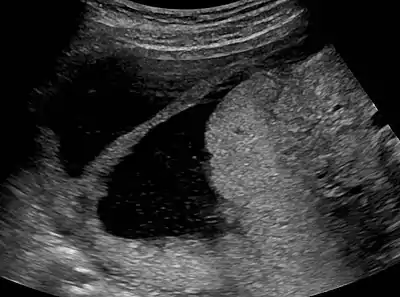

| Ultrasound view. | |

The history of a pregnancy event followed by a D&C leading to secondary amenorrhea or hypomenorrhea is typical. Hysteroscopy is the gold standard for diagnosis.[13] Imaging by sonohysterography or hysterosalpingography will reveal the extent of the scar formation. Ultrasound is not a reliable method of diagnosing Asherman's Syndrome. Hormone studies show normal levels consistent with reproductive function.